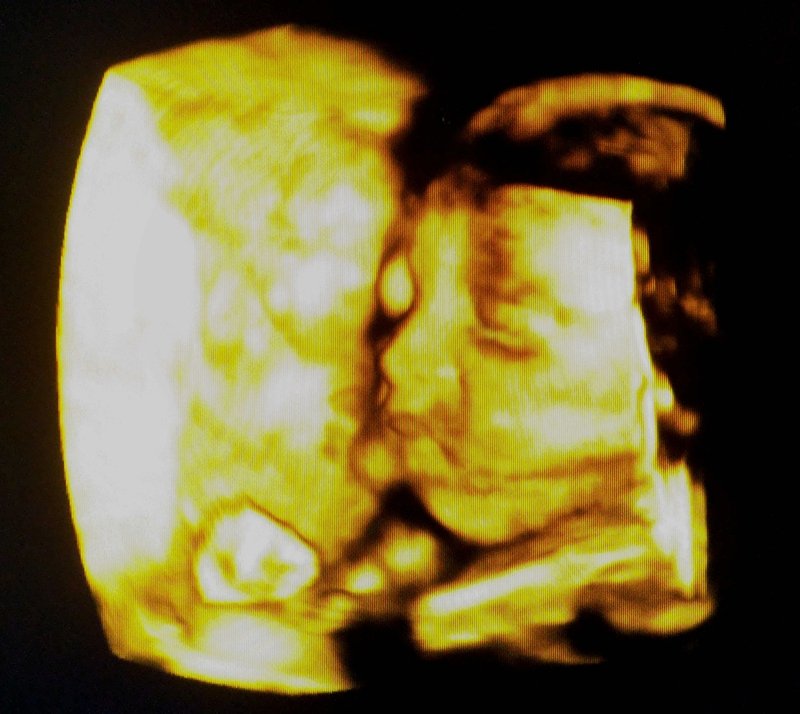

大家帮我看一下这张四维彩超图片 像男孩还是女孩 谢谢了 大家帮我看一下这张四维彩超图片 像男孩还是女孩 谢谢了 点击展开 匿名用户 2014-05-06 07:58 为您推荐: 其他回答 看起来像是男孩,好奇啥,还有一个月就见着了。安心养身体才是正点 匿名用户 2014-05-06 08:04 应该是男孩吧! 匿名用户 2014-05-06 08:04 宝宝最开始的B超图,椭圆形的是男孩 匿名用户 2014-05-06 08:03 相关问题 帮忙看看我家宝宝的四维彩超图片,像男孩还是像女孩呀?长得像妈妈哦~ 个位有经验的宝妈帮我看这张cb单男孩,女孩,十二周的 谢谢 宝妈们,早上好这是我怀孕20周加二天帮我看看是男孩女孩分享一下你们的经验谢谢这是刚拍图片